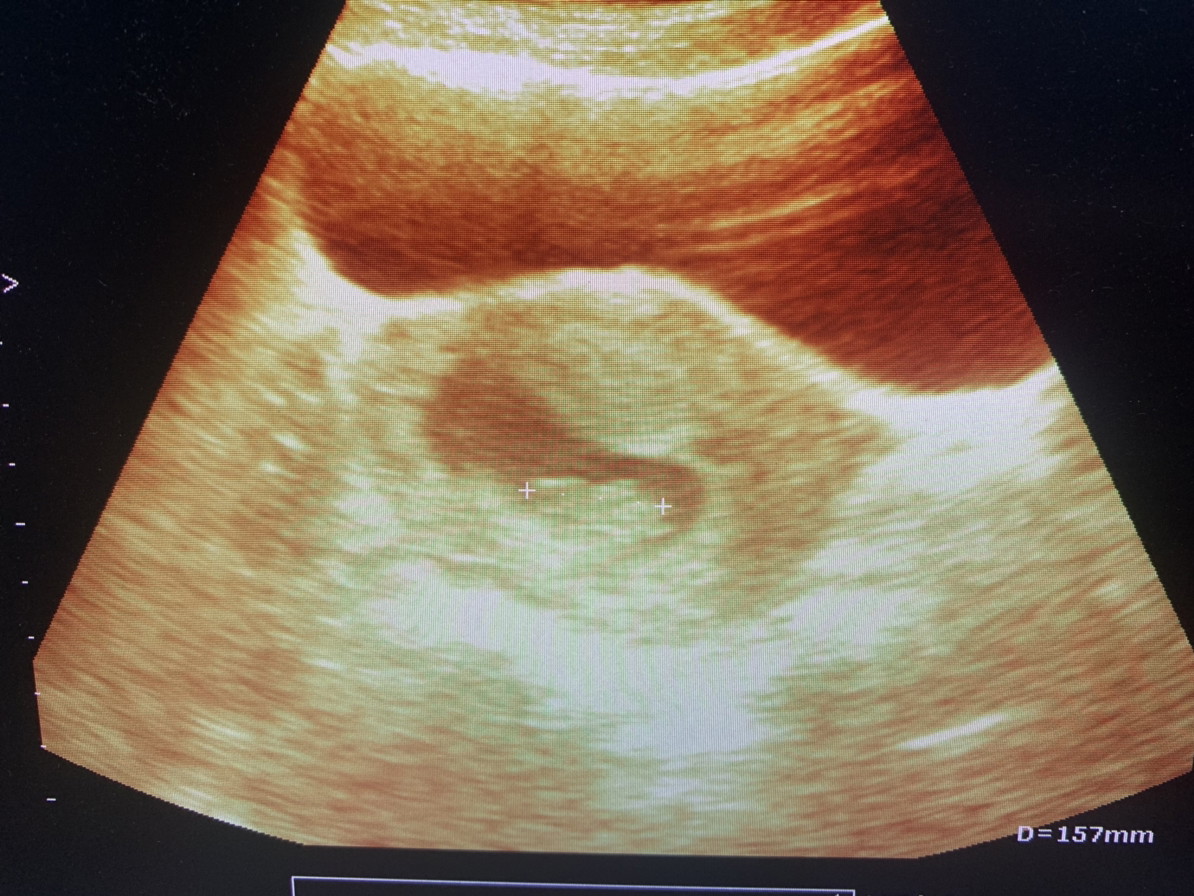

8w พอดีค่ะภาพแรก ตอนนี้ 10wค่ะ

ตอน 8 วีคค่ะ ตอนนี้ 33 วีค 5 วันค่ะ

ท้องแรก ตอนนี้14วีคแล้วค่ะ 💜

4ปีที่รอคอยค่ะ รู้ตัวก็10wแล้ว

ภาพแรกของหนู ตอนอายุครรภ์ 7W6D

ซาวตอน8weekตอนนี้36weekแล้วจ้า

ภาพแรกตอน 10 week จ้า ตอนนี้ 25 week

ตอน5วีค คะ ตอนนี้ 17+3เเล้วคะ

ตอน12วีคคะ ตอนนี้20วีคแล้ว

ภาพแรกตอน 3 เดือนค่ะ